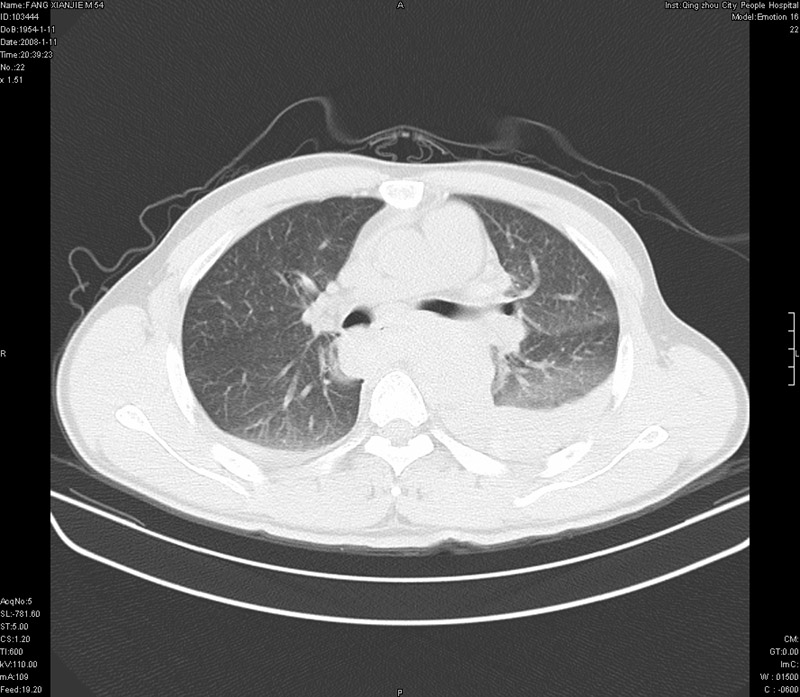

男性,40岁。胸部被车压伤伴胸痛1小时来院就诊。检查:一般情况尚可,血压110/80,胸部及上腹部压痛。结果在三天后公布。骨窗在横断位、冠矢状显示肋骨、胸椎、和胸骨未见骨折征象。

ct11308:胸部外伤1小时(证实病例) (2008-1-13 16:2)结果如下:病人入院后两小时后症状加重,8小时后在征得病人家属同意做了ct增强扫描。如下图。最终临床诊断:外伤性胸主动脉破裂并纵隔内血肿。由于有运动性伪影,胸骨在矢状面重建的图像似有骨折征,这是一种假象,我们称之为“假骨折”,这在多层ct重建中经常性遇到,必要时要结合横断图像鉴别之。现在,病人的一般情况较差,是否要手术家属尚有争议,如果手术修补,难度较大,需要专门预定制作固定支架。

当然,对于该病例,其它非重要的诊断还有:右侧少量气胸;左侧胸腔积液;左侧轻度肺挫裂伤。对于纵隔内血肿,我们曾经遇到过多例,也有怀疑主动脉的破裂,但是,均未得到具体出血部位的明确诊断。